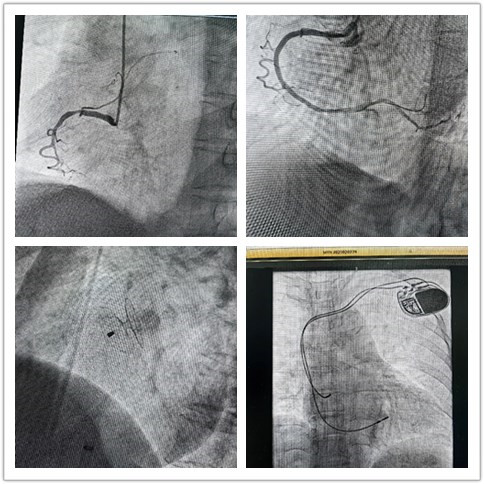

“组团式”帮扶队员—心内科邓纪钊,立即组织指导多学科团队开通胸痛绿色通道,有条不紊进行急诊术前相关检查,诊断为急性下壁心肌梗死。绕行病房,直达介入手术室,仅用32分钟顺利开通血管,患者转危为安,预后良好。

心内科救治能力和水平不断提高,业务范围不断扩展,先后完成多例卵圆孔未闭封堵、永久性心脏起搏器植入、心律失常射频消融术等。县21点策略

从2022年3月组建介入科至今,截至发稿,冠脉介入手术已逾1000例,急诊冠脉内介入治疗手术已过百例,无1例手术相关医疗事件发生。这是镇安县21点策略